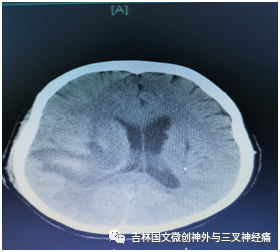

患者郝某,是一名糖尿病患者,既往有兩次腦出血病史,本次因突發(fā)意識(shí)不清于2020年11月12日急診來(lái)我院救治,經(jīng)檢查為:右側(cè)大量腦出血破入腦室,入院時(shí)患者已處于昏迷狀態(tài),呼吸、咳痰費(fèi)力,左側(cè)巴花斯基征陽(yáng)性??紤]病人為第三次腦出血,可能存在血管畸形等血管病變情況,入院后立即安排頭部CTA檢查,結(jié)果回報(bào)未見(jiàn)明顯動(dòng)脈瘤及血管畸形等情況,考慮為高血壓、動(dòng)脈硬化引起腦出血,為了減少副損傷,經(jīng)與家屬溝通,我們采取了血腫腔置管液化引流手術(shù)治療。

術(shù)后引流良好,意識(shí)逐漸轉(zhuǎn)清,根據(jù)復(fù)查頭部CT結(jié)果拔出血腫腔引流,因腦室內(nèi)仍有大量血液,防止腦積水的發(fā)生,術(shù)后又采取了腰大池引流治療,徹底把腦室內(nèi)積血引流干凈;病人盡管意識(shí)恢復(fù),但咳痰能力差,為了保障呼吸道通暢,給予氣管切開(kāi)促進(jìn)排痰,病情逐漸好轉(zhuǎn)。